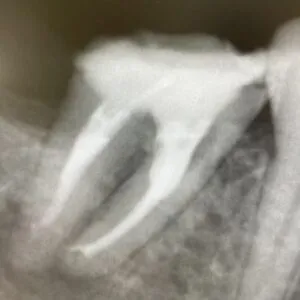

赤◯部分の破折ファイルは、マイクロスコープを使って取り除いたあとに、根管治療を行いました。

抜歯することなく治療が終了しました😄

破折ファイルを取り除くためには、機器や器具、高い技術と時間が必要です。

当院は、根管治療に力を入れておりますので、マイクロスコープや多数の超音波チップを用意しています。

1回の診療につき1時間程度かけて地道に破折ファイルを除去していきます。

もちろん回数がかかることもありますし、根管の形状や状態によっては更なる治療が必要になることもあります。